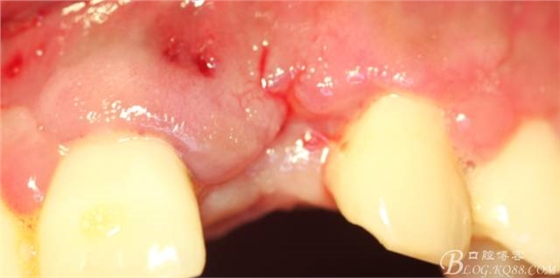

事實證明,我的做法沒有錯誤,一個月后,軟組織健康愈合。鄰牙軟組織沒有退縮。

4個月后,唇側(cè)豐滿度尚可,與鄰牙之間齦乳頭完整。